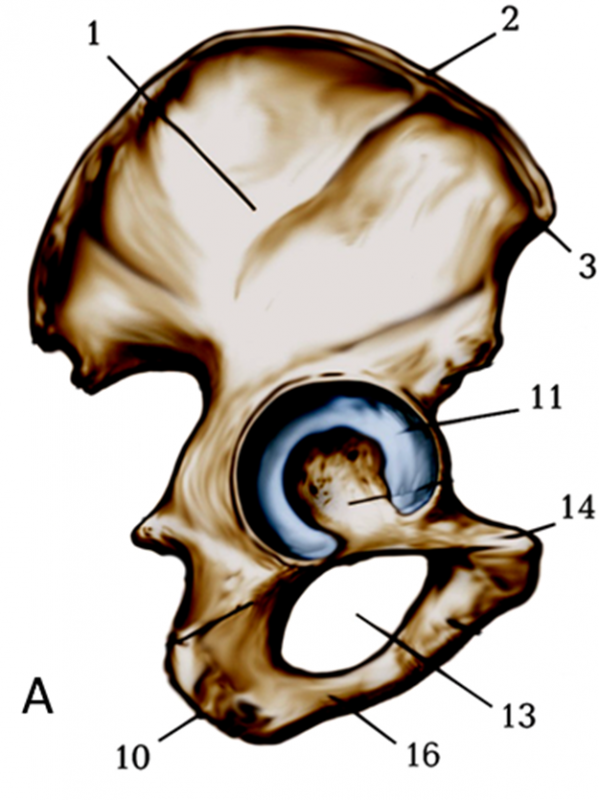

ЯКА КІСТКА ТА ЯКА ЇЇ ЧАСТИНА УТВОРЮЄ БІЧНУ СТІНКУ ВЕЛИКОГО ТАЗУ?

варіанти відповідей

КРИЛО

OS ILEUM

ДЕ ВИ БАЧИТЕ ЕЛЕМЕНТ КІСТКИ, ЗНАННЯ ЯКОГО НЕОБХІДНЕ В АКУШЕРСТВІ ДЛЯ ВИМІРЮВАННЯ РОЗМІРІВ ВЕЛИКОГО ТАЗУ? (ВЕРТЛЮГОВА ДИСТАНЦІЯ).

СУГЛОБОВА ПОВЕРХНЯ ТАЗОВОЇ КІСТКИ З'ЄДНУЄТЬСЯ З ... КІСТКОЮ І УТВОРЮЄ ... СУГЛОБ

З FEMUR

З OS PUBIS

З OS ISCHII

З OS ILEUM

УТВОРЮЄ КЛУБОВО-СТЕГНОВИЙ СУГЛОБ

УТВОРЮЄ КУЛЬШОВИЙ СУГЛОБ

УТВОРЮЄ ТАЗОВИЙ СУГЛОБ

УТВОРЮЄ ТАЗОСТЕГНОВИЙ СУГЛОБ